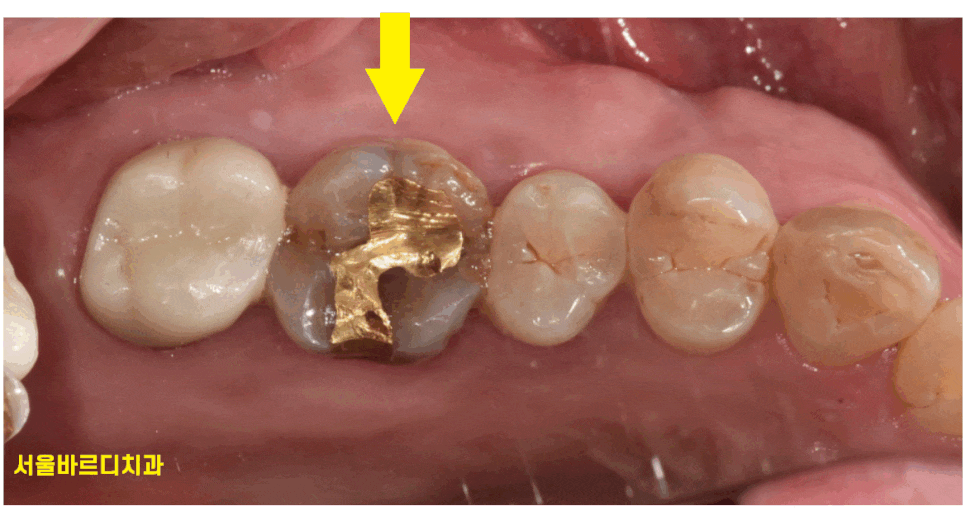

예전에 치료했던 금 인레이 치아 주변이 까만 것이

한눈에 보기에도 충치가 있었습니다.

좀 더 자세히 바람도 불어보고 보았더니

이차 충치네요.

금 인레이 벌어진 틈새 사이로 충치가 생겼습니다.

이차 충치

충치가 두번 생겼다는 말입니다.

한번 치료한 곳에서 또 충치..

금 인레이에서 자주 볼 수 있습니다.